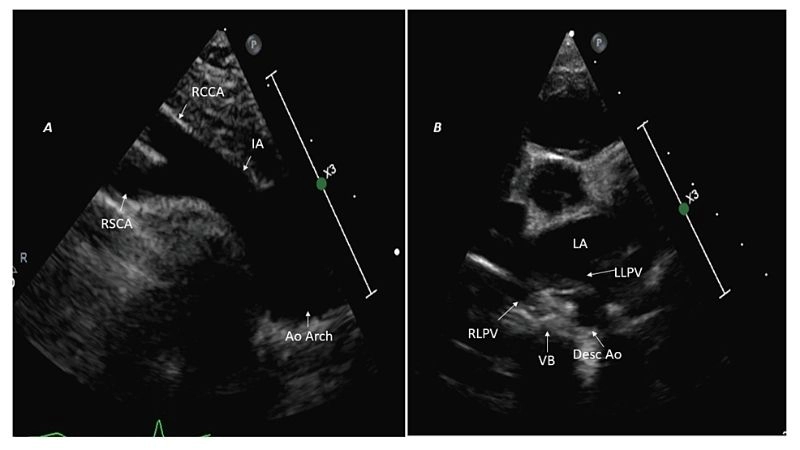

Images visual examples of vascular rings

Vascular rings are congenital vascular anomalies where abnormal aortic arch structures encircle the trachea or esophagus. Visual images help illustrate the compression they cause on vital passages.